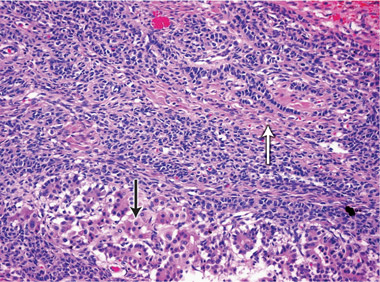

At 59 years of age, a laparotomy was performed and the patient was found to have a large left adnexal mass (Box 1, A) and a normally formed uterus. The mass was removed and a subtotal hysterectomy performed as there was no distinct lower margin of the cervix (Box 1, B). The patient was informed of the operative findings and the diagnosis of intersex. Peripheral blood karyotyping showed a 46,XY genotype. The histopathology of the gonadal tumour showed a sex cord-stromal tumour of indeterminate differentiation (Box 2). The histopathology of the uterus showed simple endometrial hyperplasia. The patient was treated with postoperative chemotherapy, but died 18 months later.

The risk of malignancy in dysgenetic gonads is significantly increased in some patients with DSD.8 The presence of the SPY gene on the GBY region of the Y chromosome is a prerequisite for malignant transformation.9 Tumours can arise in any of the gonadal cells or their precursors.8 Precursor lesions for the development of cancers occur as carcinoma-in-situ in testicular tissue and gonadoblastoma in undifferentiated gonadal tissue. A number of malignant tumour types may occur in dysgenetic gonads.8,10 These include germ cell tumours and sex cord-stromal tumours. Patients presenting with abdominal tumours in dysgenetic gonads in adulthood provide histopathologists with complex diagnostic dilemmas. Histopathological examination of the tumour in our case showed mixed elements, with cells resembling ovarian follicles, testicular tunica, granulosa cells, Sertoli cells and Leydig cells. No germ cell components were identified. The final consensus was a diagnosis of malignant sex cord-stromal tumour of indeterminate differentiation.

We thank Peter Russell of Douglass Hanly Moir Pathology for assisting with the interpretation of the histopathology results, and with the preparation of the microscopic illustrations.